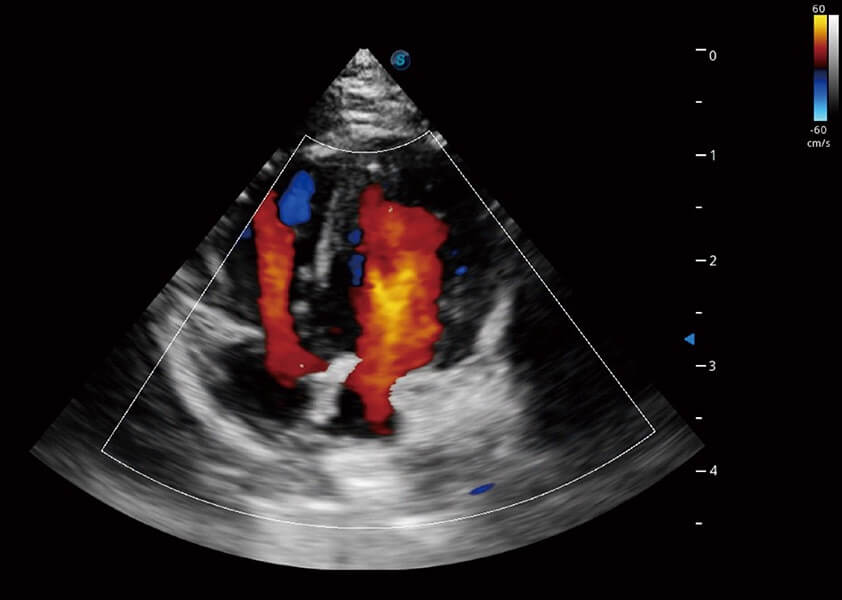

ProPet 60 作为一款高端台式动物超声设备,为动物医生的日常诊断提供了一系列贴合动物临床需求、解决临床实际问题的高级成像功能。凭借全系列高清探头,满足医生对腹部、心脏、生殖、浅表、肌骨等成像的所有需求,切实帮助您提升检查效率,提高诊断信心。

兽用彩色多普勒超声诊断系统